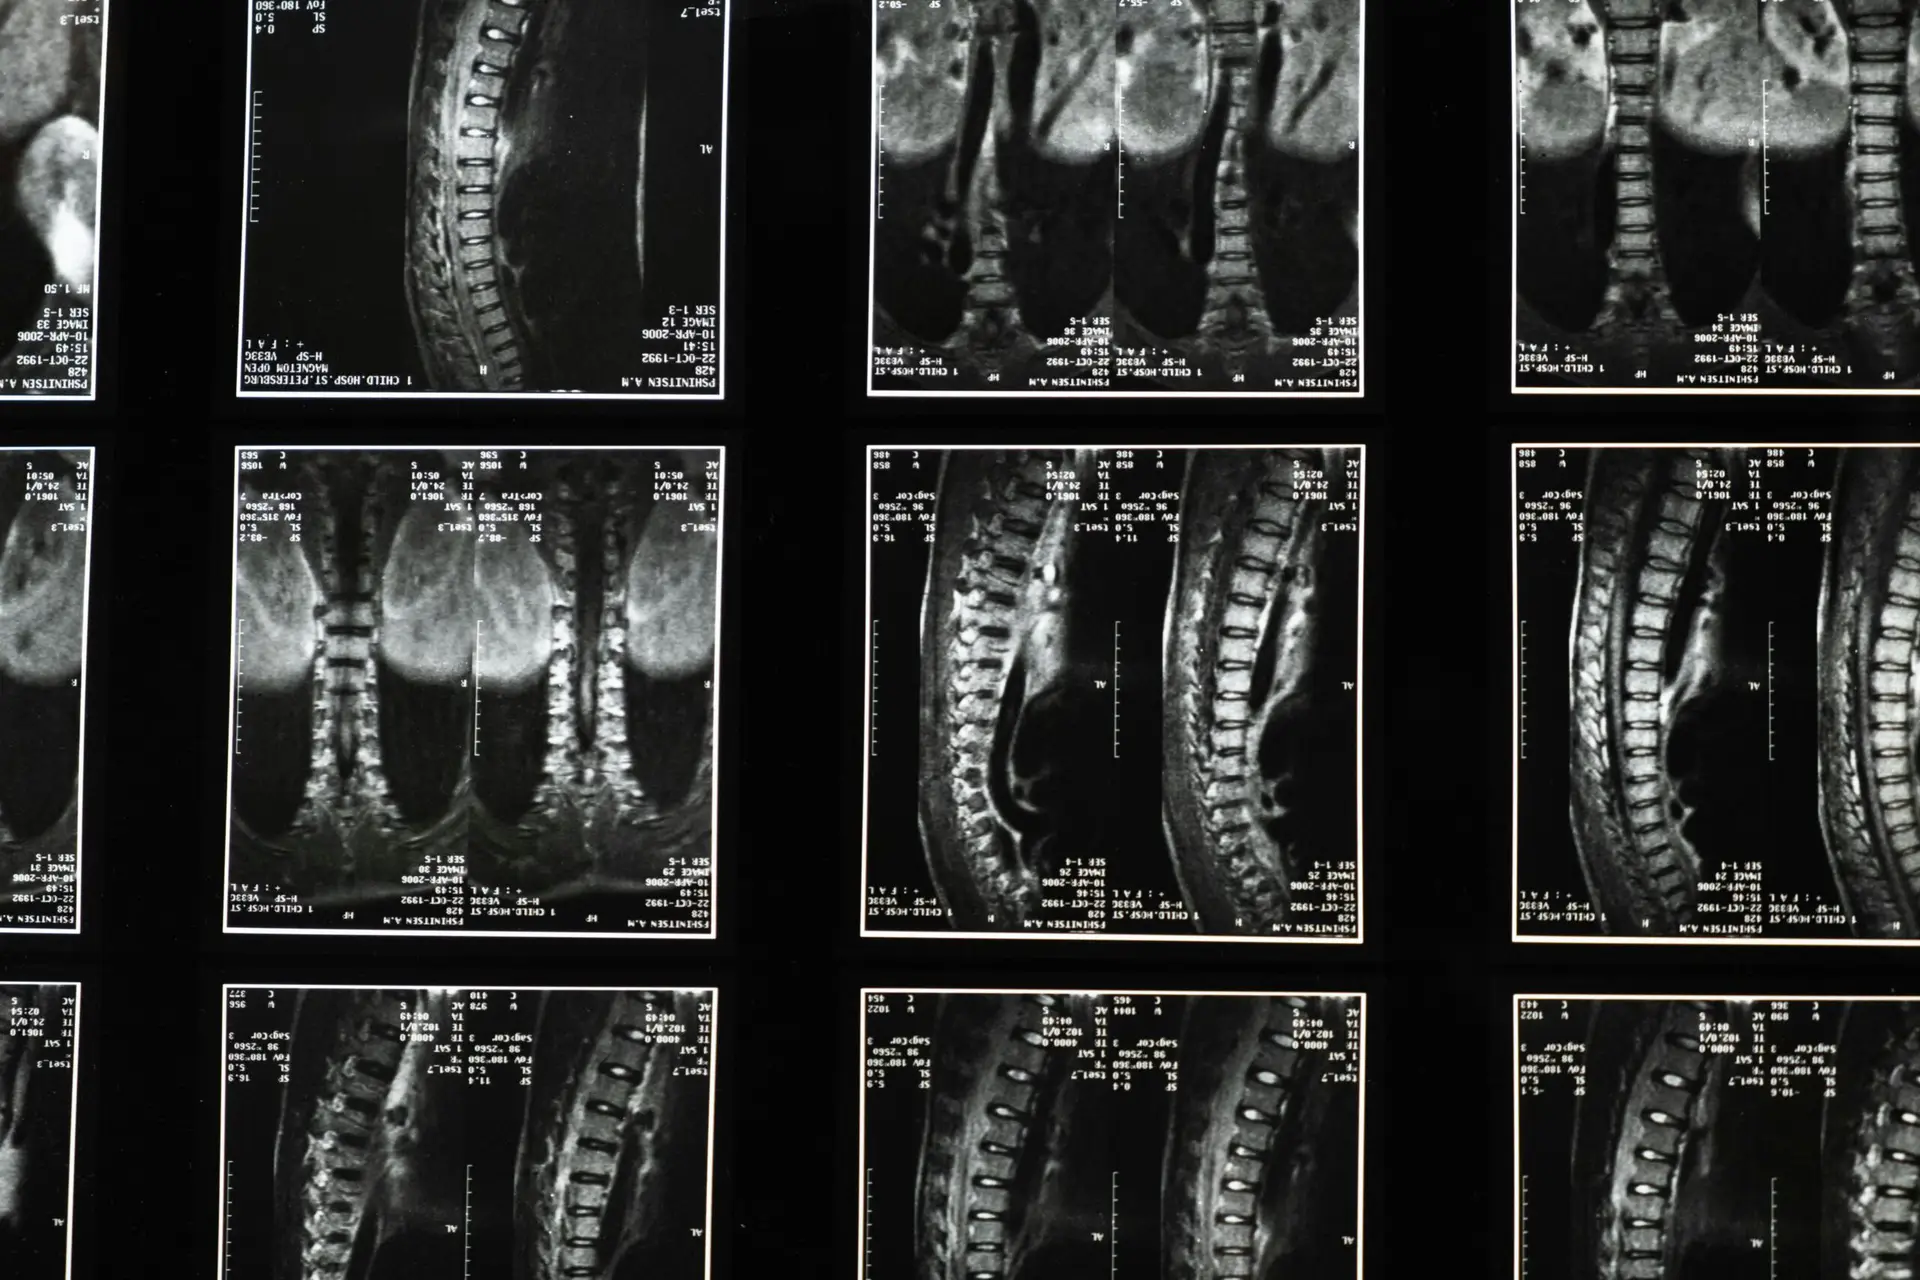

Scoliosis Doctor Near Me: If you’ve been searching “scoliosis doctor near me” and wondering whether there’s a gentle, precise, natural path to help you or your child, you’re in the right place. At Lavender Family Chiropractic in Sarasota and Lakewood Ranch, our...